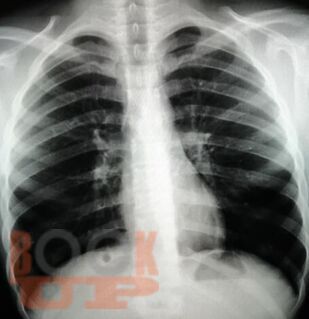

Учебное пособие составлено в соответствии с требованиями ФГОС ВО по специальностям 31.05.01 Лечебное дело и 31.05.02 Педиатрия, рабочей программы дисциплины «Фтизиатрия» (2018). В пособии собраны воедино и обобщены сведения о лучевой диагностике туберкулеза органов дыхания, включена клиническая классификация туберкулеза, иллюстрированная рентгенограммами больных, лечившихся в КГБУЗ «Красноярском краевом противотуберкулезном диспансере №1» с 1980-х г. по настоящее время.